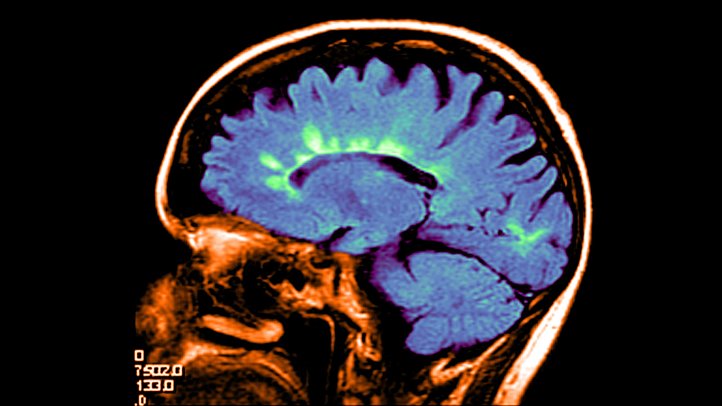

Também na ressonância magnética (RM) que é uma técnica de diagnóstico que utiliza campos magnéticos intensos, que permite obter imagens do interior do corpo

A Estimulação Magnética Transcraniana (EMT) consiste numa técnica de estimulação cerebral, que recorre a campos magnéticos gerados por uma bobina de estimulação, com o propósito de estimular ou inibir zonas específicas do cérebro que estão correlacionadas com determinadas patologias. Esta técnica terapêutica tem-se revelado como uma alternativa segura aos tratamentos convencionais e com resultados positivos para diferentes quadros clínicos